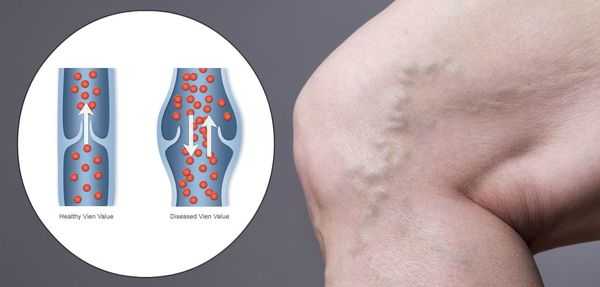

Патогенез хронической венозной недостаточности

Патогенез ХВН очень специфичен. У здорового человека отток крови происходит через глубокие вены голени. Благодаря совместной работе постоянно сокращающейся и расслабляющейся скелетной мускулатуры и клапанного аппарата кровь направляется к сердцу, где она насыщается кислородом. В процессе этой работы гладкая скелетная мускулатура усиливает давление на вены, а клапанная система, которая состоит из смыкающихся створок, не позволяет крови поддастся силе тяжести.

Из-за длительно существующих факторов риска возникает венозная гипертензия, происходит расширение и выпячивание стенки вен. Створки клапанов расходятся и не могут препятствовать патологическому оттоку крови. Увеличенный объём крови сильнее давит на стенку вены, поэтому вена расширяется. Если не начать лечение, вена продолжит расширяться. Стенки сосудов начнут стремительно терять свою эластичность, их проницаемость увеличится. Через стенки в окружающие ткани будут выходить элементы крови, плазма. Таким образом возникает отёк тканей, что еще больше обедняет их кислородом. В тканях накапливаются свободные радикалы, медиаторы воспаления, запускается механизм активации лейкоцитов. Это нарушает питание и обмен веществ тканей. Конечным итогом становится образование «венозных» трофических язв, что существенно снижает качество жизни пациента. [4] [6]